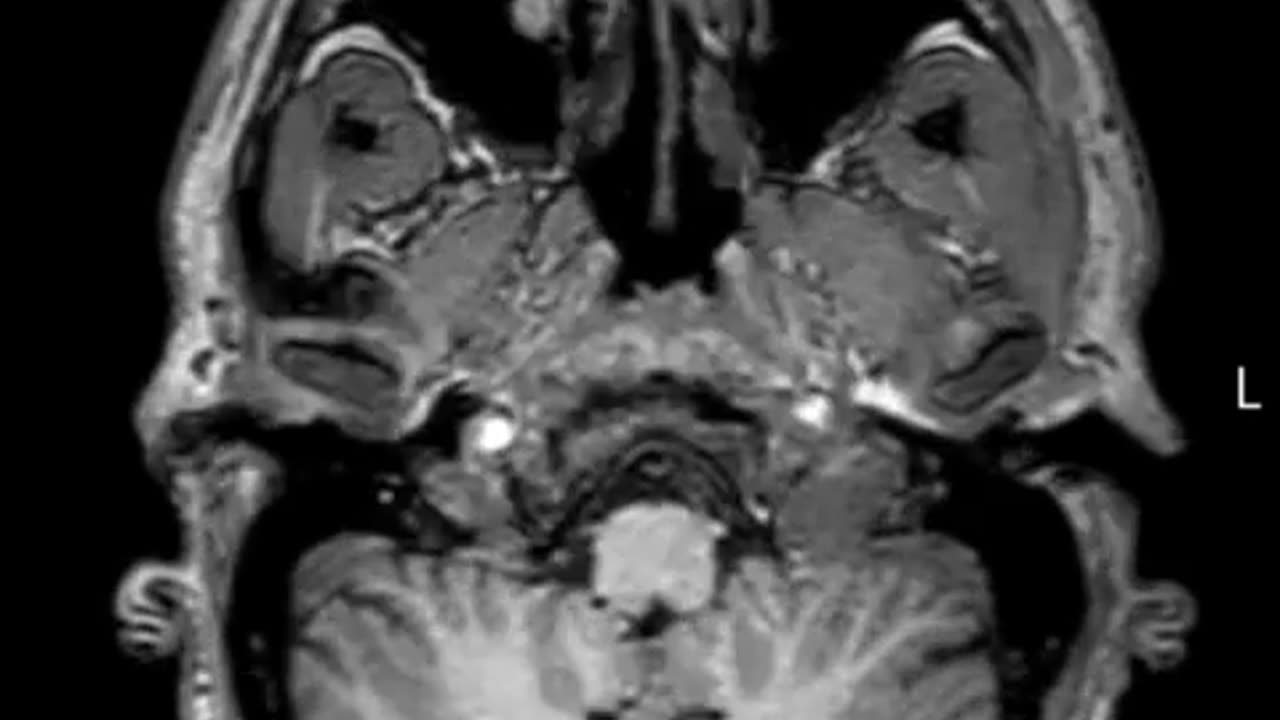

🤯✨ Jaw-Dropping MRI of My Head From Bottom to Top! | FeedMyCuriosity

This astonishing MRI scan offers a unique bottom-up view of the human head, revealing details you’ve never seen before. What surprises do you think the scan shows? Let us know! 👉 To feed your curiosity with more amazing content, make sure you Like & Subscribe! #Medical #MRI #Anatomy